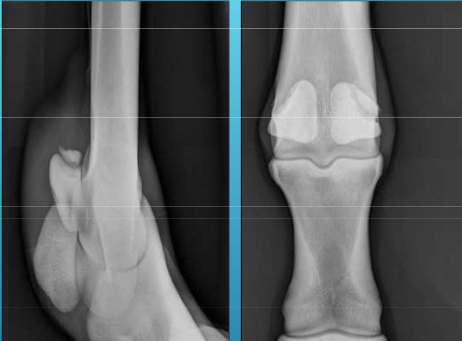

What is the view, what are the bones?

Dorsopalmar view

4th carpal bone and Metacarpal 4